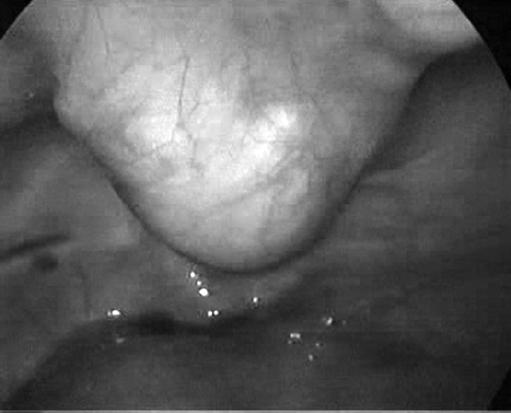

Bladder pheochromocytomas are extremely rare and constitute less than 5% of bladder tumors. The initial symptoms of the patient are mostly nonspecific caused by hypertension. The postmicturition hypertensive crisis is the typical warning sign of this disease. In this article, we present a 29-year-old female having hypertensive attacks following micturition. Radiological imaging techniques revealed a 3 x 3 x 4-cm bladder tumor that was hormonally active. This is the first case reported of bladder pheochromocytoma that was laparoscopically treated without using the adjunct transurethral resection. The postoperative follow-up of the patient confirms the success of the surgical procedure.

膀胱嗜铬细胞瘤极为罕见,占膀胱肿瘤的比例不到5%。患者的初始症状大多由高血压引起,缺乏特异性。排尿后高血压危象是该病的典型警示信号。在本文中,我们介绍了一名29岁的女性,她在排尿后出现高血压发作。放射影像学检查发现一个3×3×4厘米大小、具有激素活性的膀胱肿瘤。这是首例报道的经腹腔镜治疗且未辅助经尿道切除术的膀胱嗜铬细胞瘤病例。对该患者的术后随访证实了手术的成功。